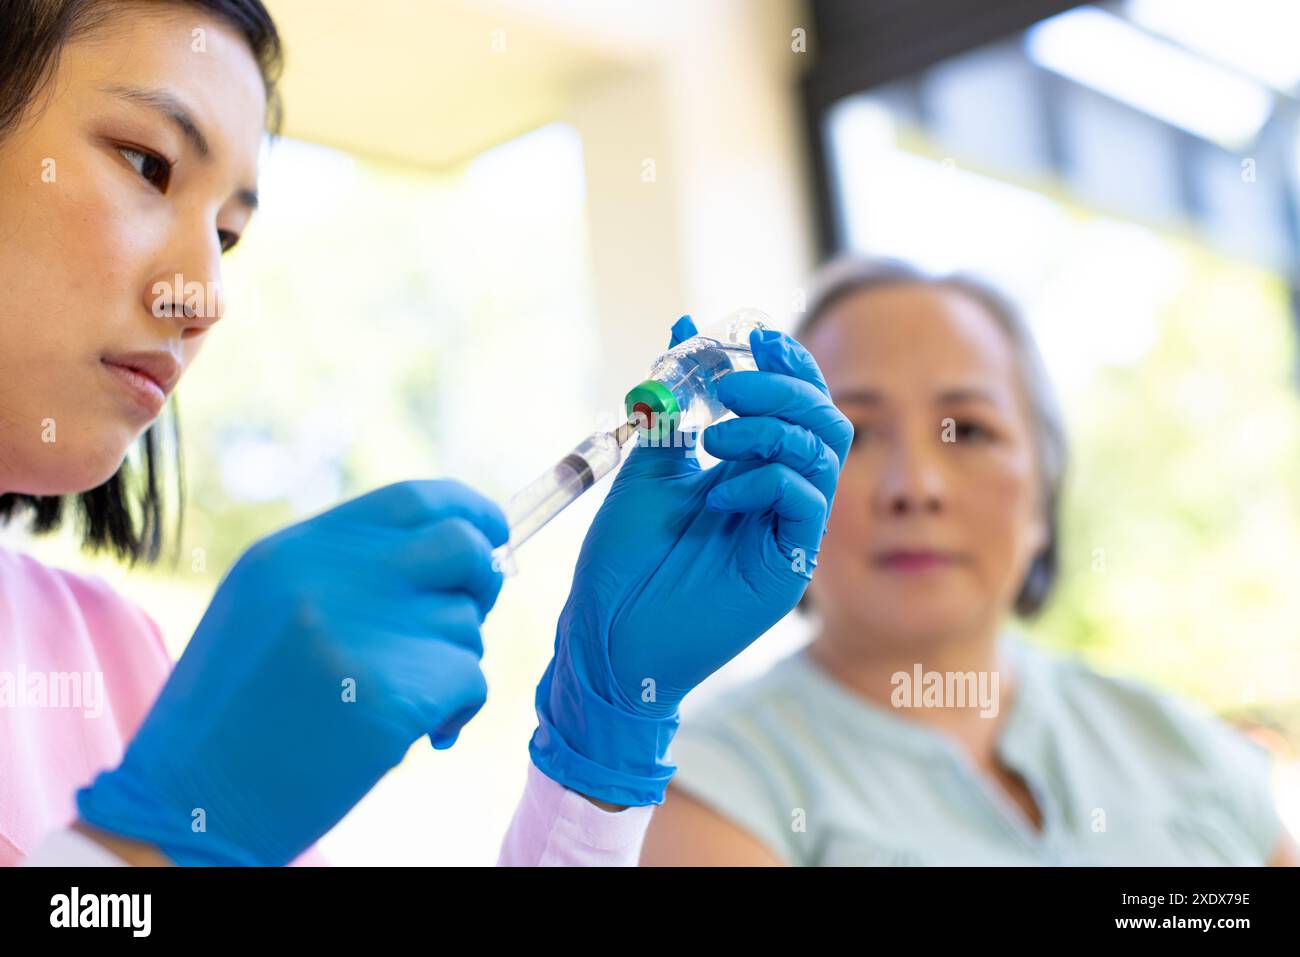

Female nurse preparing syringe for senior woman during home visit for medical care Stock Photohttps://www.alamy.com/image-license-details/?v=1https://www.alamy.com/female-nurse-preparing-syringe-for-senior-woman-during-home-visit-for-medical-care-image610929914.html

Female nurse preparing syringe for senior woman during home visit for medical care Stock Photohttps://www.alamy.com/image-license-details/?v=1https://www.alamy.com/female-nurse-preparing-syringe-for-senior-woman-during-home-visit-for-medical-care-image610929914.htmlRF2XDX79E–Female nurse preparing syringe for senior woman during home visit for medical care